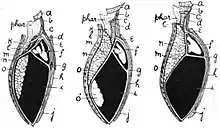

The diaphragm is the main muscle of respiration and functions in breathing. During inhalation, the diaphragm contracts and moves in the inferior direction, enlarging the volume of the thoracic cavity and reducing intra-thoracic pressure (the external intercostal muscles also participate in this enlargement), forcing the lungs to expand. In other words, the diaphragm's movement downwards creates a partial vacuum in the thoracic cavity, which forces the lungs to expand to fill the void, drawing air in the process.

Cavity expansion happens in two extremes, along with intermediary forms. When the lower ribs are stabilized and the central tendon of the diaphragm is mobile, a contraction brings the insertion (central tendon) towards the origins and pushes the lower cavity towards the pelvis, allowing the thoracic cavity to expand downward. This is often called belly breathing. When the central tendon is stabilized and the lower ribs are mobile, a contraction lifts the origins (ribs) up towards the insertion (central tendon) which works in conjunction with other muscles to allow the ribs to slide and the thoracic cavity to expand laterally and upwards.